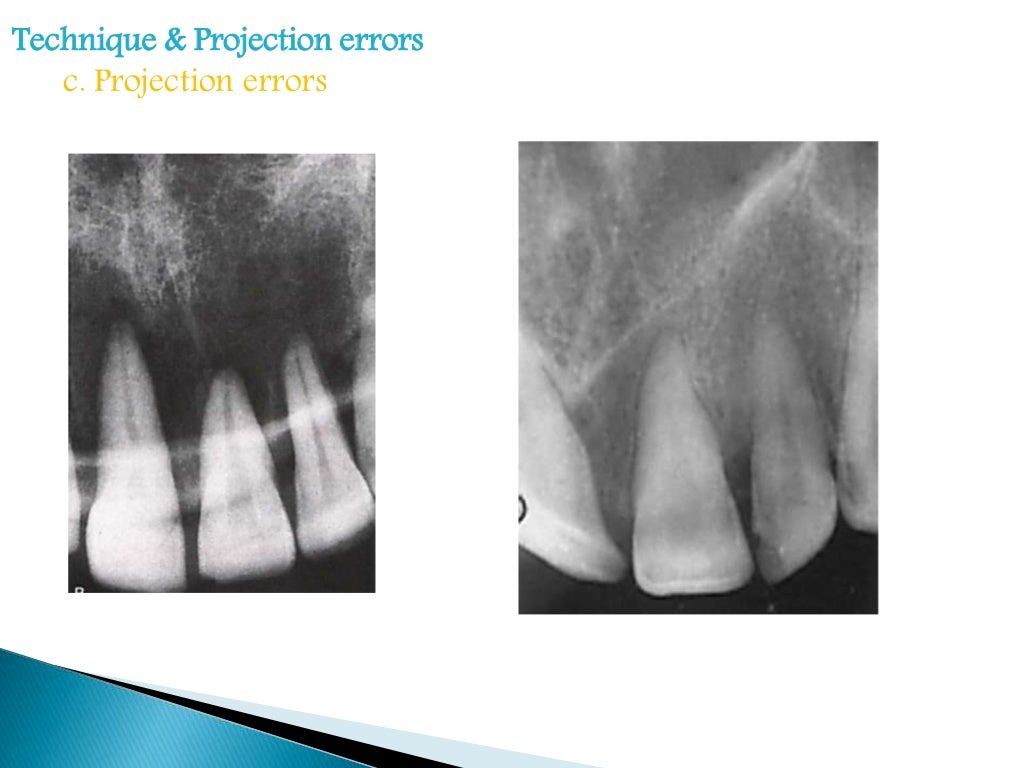

Radiographic errors and artifacts